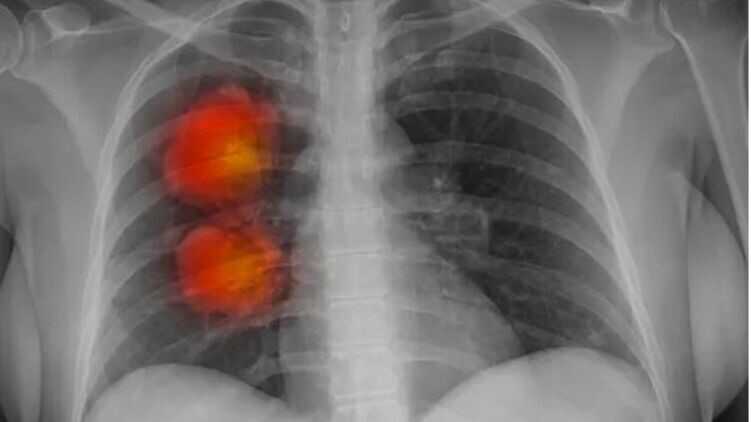

Інструмент штучного інтелекту був розроблений експертами фонду Royal Marsden NHS, Інституту дослідження раку в Лондоні та Імперського коледжу Лондона. Він може визначити, чи аномальні новоутворення, виявлені на КТ, злоякісними.

Команда використовувала комп’ютерну томографію близько 500 пацієнтів із великими вузлами в легенях розробки алгоритму штучного інтелекту. Цей метод може мати життєво важливу інформацію з медичних зображень, які важко помітити людському оку.

Згідно з початковими результатами, модель ІІ, мабуть, точно ідентифікує великі ракові вузлики в легенях.